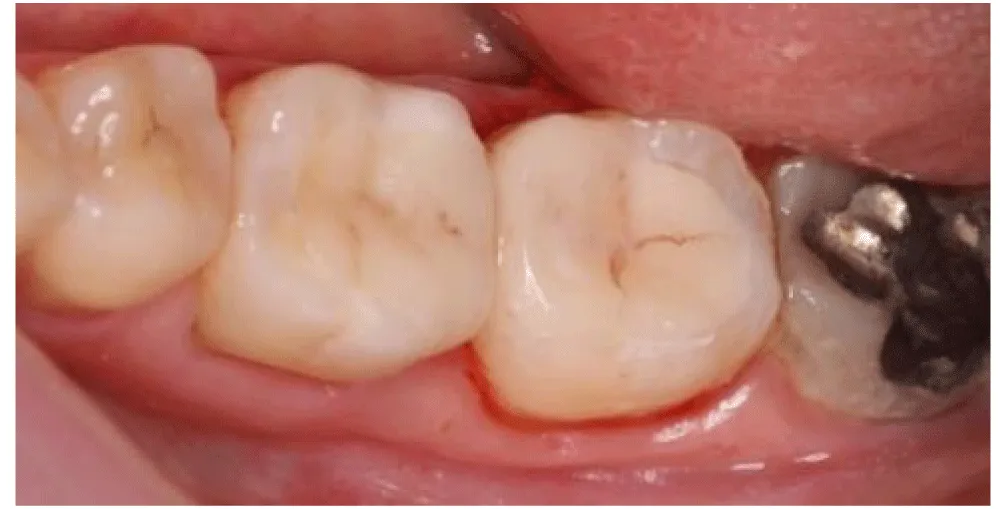

Sufficient enamel was preserved at the margins because bonded margins to enamel give superior and more durable adhesion. Deep Margin elevation was performed in the first molar. During the stage of cementation, Restorations were etched (hydrofluoric acid for ceramics) and silanized. Tooth surfaces were selectively etched, and a universal adhesive was applied. Duale Resin cement was used for bonding under controlled isolation (Figure 5-7). Restorations were finally light-cured from all aspects, and glycerin was applied in the margins to protect the marginal fit (Figure 8). At the 2-week follow-up, the patient reported complete disappearance of pain. No bleeding was observed during hygiene procedures. The interproximal area was restored, and the architecture was established with a continuous adhesive surface and optimal marginal integrity (Figure 9).